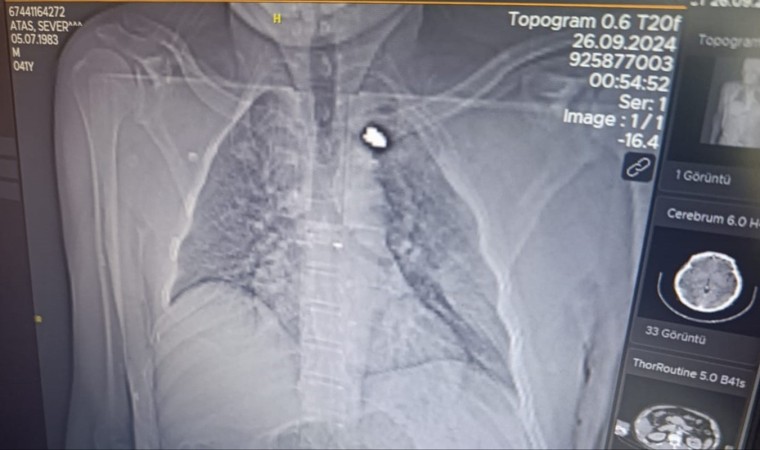

Olay, akşam saatlerinde Birecik ilçesine bağlı Karşıyaka Mahallesinde meydana geldi. İddiaya göre, damda uyuyan Sever Ataş’a (43), nereden ateşlendiği belirlenemeyen bir yorgun mermi isabet etti. Göğsüne isabet eden mermi ile yaralanan Ataş kanlar içerisinde kaldı. Olayı fark eden yakınlarının ihbarı ile ambulansla Birecik Devlet Hastanesi’ne kaldırılan Ataş, hayati tehlikesi bulunduğu gerekçesiyle Şanlıurfa Mehmet Akif İnan Eğitim ve Araştırma Hastanesine sevk edildi. Tedavisi devam eden adama isabet eden kurşunun göğsünde takılı kaldığı görüldü. Polis silahı ateşleyen kişinin tespit edilmesi için çalışma başlattı.